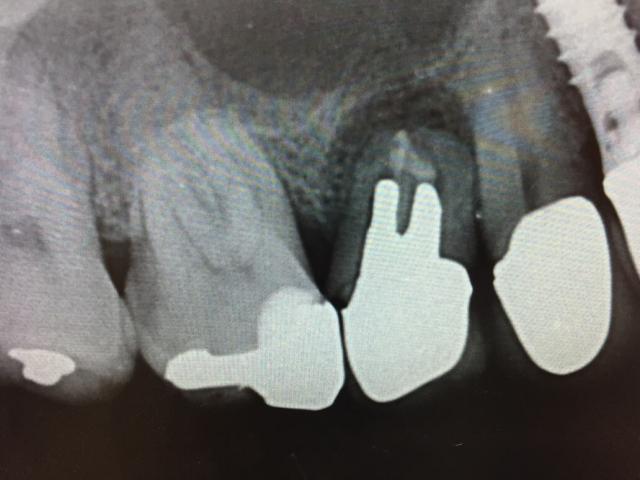

本日は午後から右上5番欠損の

インプラント手術を行いました。

インプラント治療です。今回のケースは3カ月前に

根尖病巣のために

抜歯となった部位に

インプラントをおこないました。

本日のオペデータ

手術時間13分間

右上5番 直径4.8ミリ×10ミリ SP SLActive

ストローマンインプラント使用

フラップレス法+ソケットリフト法併用